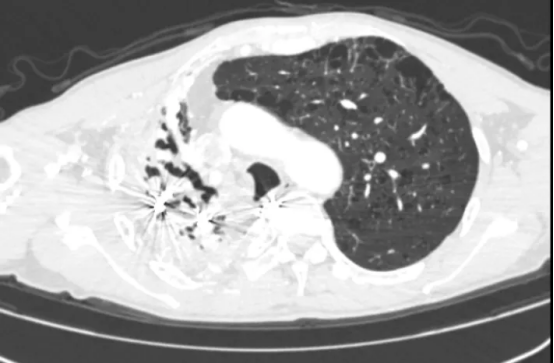

术前影像(左右滑动查看更多)

该患者为61岁男性,肺部病情错综复杂。4年前确诊肺结核后因治疗不规范,发展为“利福平耐药”结核,病情持续恶化。2年来反复咯血,虽经3次支气管动脉栓塞术暂时控制,但病灶顽固,收治入院时已形成多重诊断:毁损肺(右上)、右肺下叶鳞癌(背段)、肺曲霉菌病、陈旧性肺结核。其右肺上叶完全丧失功能,并与胸壁形成致密粘连,医学上称为“毁损肺”——胸外科领域公认的极高难度手术。